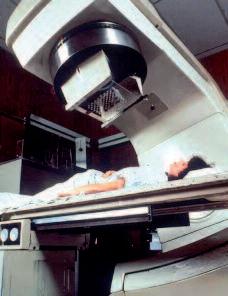

l'obiettivo terapeutico della chemioterapia e della radioterapia è quello di uccidere le cellule tumorali intossicando tutto il corpo

La radioterapia e la chemioterapia, utilizzate dalla medicina convenzionale fino ad oggi per combattere il cancro, hanno un comune effetto ‘terapeutico’: assieme alle cellule tumorali uccidono anche miliardi di cellule sane. Queste procedure altamente tossiche danneggiano indiscriminatamente tutte le cellule del corpo dei pazienti e sono, quindi, terapie “non selettive” sulle cellule cancerogene.

A peggiorare le cose, la chemioterapia colpisce in particolare le cellule sane del nostro corpo che si moltiplicano rapidamente, ad esempio i globuli bianchi del sistema immunitario. Così, quando il corpo di un malato di cancro ha maggiore necessità di una difesa efficace, le cellule immunitarie vengono sistematicamente distrutte da questi farmaci molto tossici.

Anche un profano può capire che se la medicina deve ricorrere ad una terapia non selettiva, ciò sta ad indicare solo una cosa: le cause e i decorsi della malattia non sono propriamente compresi, quindi non possono essere definite terapie efficaci che agiscono specificamente sulle cellule tumorali.

Per ingannare i pazienti e fornire false speranze, la medicina convenzionale utilizza i termini ‘chemio-terapia’ e ‘radio-terapia’, quando in realtà non esiste nessuna ‘terapia’ efficace. L’uso della terapia convenzionale contro il cancro degli ultimi decenni può essere definito come un fallimento della medicina.

Radiote rapi a e chemi ot erapia uc cidono le ce llul e tumoral i e anc he l e cel lule s ane.

La chemioterapia è così tossica che è necessario l’aiuto di un catetere speciale per iniettarla nelle vene dei pazienti.